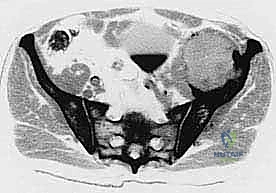

- التصوير المقطعي المحوسب (CT Scan): يقدم صوراً ثلاثية الأبعاد تُظهر بدقة متناهية مدى تدمير القشرة العظمية، وهو الفحص الأهم للتخطيط الجراحي وتحديد خطر حدوث الكسور المرضية.

- التصوير بالرنين المغناطيسي (MRI): الفحص الأفضل لتقييم امتداد الورم خارج العظم إلى الأنسجة الرخوة (العضلات، الأوعية الدموية، الأعصاب) وتقييم مدى إصابة نخاع العظم.

- الخزعة (Biopsy): في حال كان الورم في الحوض هو أول ظهور للسرطان (سرطان أولي مجهول المصدر)، يتم أخذ عينة من الأنسجة تحت إرشاد الأشعة المقطعية لتحديد نوع الخلايا السرطانية بدقة.

عندما يغزو السرطان منطقة الحوض، فإنه لا يكتفي بتدمير البنية العظمية الصلبة فحسب، بل يتسبب في سلسلة من المضاعفات المنهكة. يشمل ذلك الآلام الميكانيكية والبيولوجية الشديدة التي لا تستجيب للمسكنات التقليدية، وفقدان القدرة على المشي أو تحمل الوزن، فضلاً عن الخطر الداهم بحدوث "الكسور المرضية" – وهي كسور تحدث نتيجة إجهاد بسيط على عظم نخرة الورم وأضعفه. ونظراً لاتساع تجويف الحوض، ومرونة العضلات والأعضاء المحيطة به، قد تنمو هذه الأورام لأحجام كبيرة (أورام عملاقة) قبل أن تظهر أعراضها بوضوح، مما يجعل التدخل الطبي المتأخر أكثر تعقيداً.

- أورام الحُق (Acetabulum): هذه هي الحالات الأكثر تعقيداً وإلحاحاً. تدمير سقف الحُق يعني أن رأس عظم الفخذ سيندفع داخل تجويف الحوض عند محاولة المريض الوقوف، مما يسبب ألماً يفوق الوصف وقصراً في الطرف السفلي. تتطلب هذه الحالات خبرة جراحية استثنائية لإعادة بناء التجويف باستخدام الإسمنت العظمي، الدعامات المعدنية، أو المفاصل الصناعية المخصصة (Custom-made Endoprostheses).